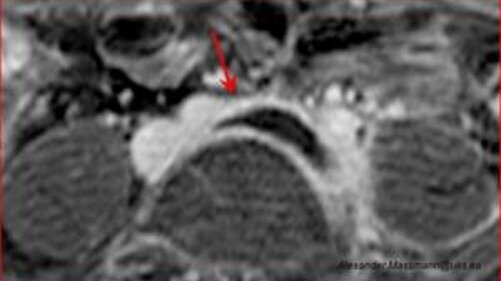

Hier ist das verschlossene Gefäß, in diesem Fall die Beckenvene (Vena iliaca), im Querschnitt zu sehen (mit Pfeil markierter schwarzer Kreis). Das Blutgerinnsel füllt die Vene vollständig aus.